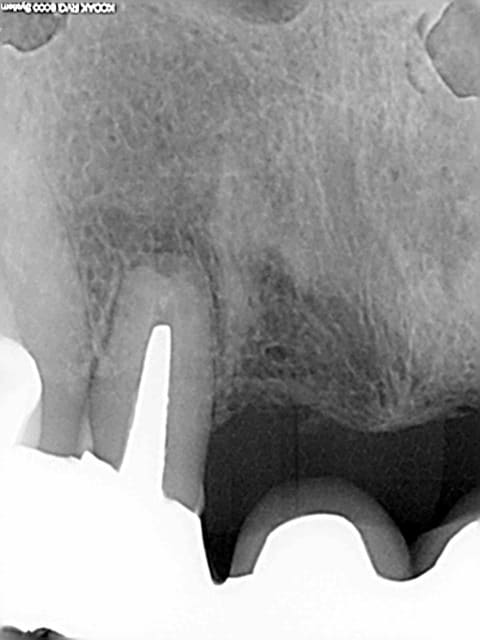

Je reçois ce matin ce mail plutôt désagréable, intitulé "votre devis hors norme", suite à une consultation en juillet pour un abcès sur la 12 (je joins les radios).

Le choix thérapeutique dépend de la balance bénéfice/risque. Pour moi la racine de la 12 n'est pas conservable (et donc le bridge non plus) car la racine est très courte et le tenon est très long. La résection apicale raccourcit encore la racine, et raccourcit d'autant la durée de vie de cette racine. J'ai donc écarté ce choix thérapeutique car il s'agissait pour moi de reculer pour mieux sauter. Mais peut-être me suis-je trompé, après tout je ne suis pas encore un chirurgien dentiste de renom. Seul le temps pourra dire si j'avais tord ou raison.

Sauf que la solution de la chir apicale n'existe pas dans ce cas là. Pour moi, la dent n'est pas conservable point. Car ratio couronne/racine de 3 pour 1 aggravé par une chir apicale, car pas 5 mm de gutta entre le tenon et l'apex, car gros risque de fracture de la racine.